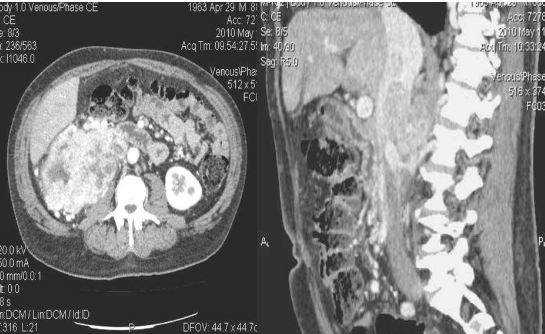

последствия травм - повреждения сосудов, разрывы фиброзной капсулы, паренхимы;

- при травмах живота или спины;

КТ хорошо показывает скелет и полые органы, которые заполненные жидкостью и воздухом. Это и делает процедуру информативной при экстренной диагностике травм с внутренним кровотечением.

- травм почек и мочеточников;

- оценки состояния при травмах забрюшинного пространства.